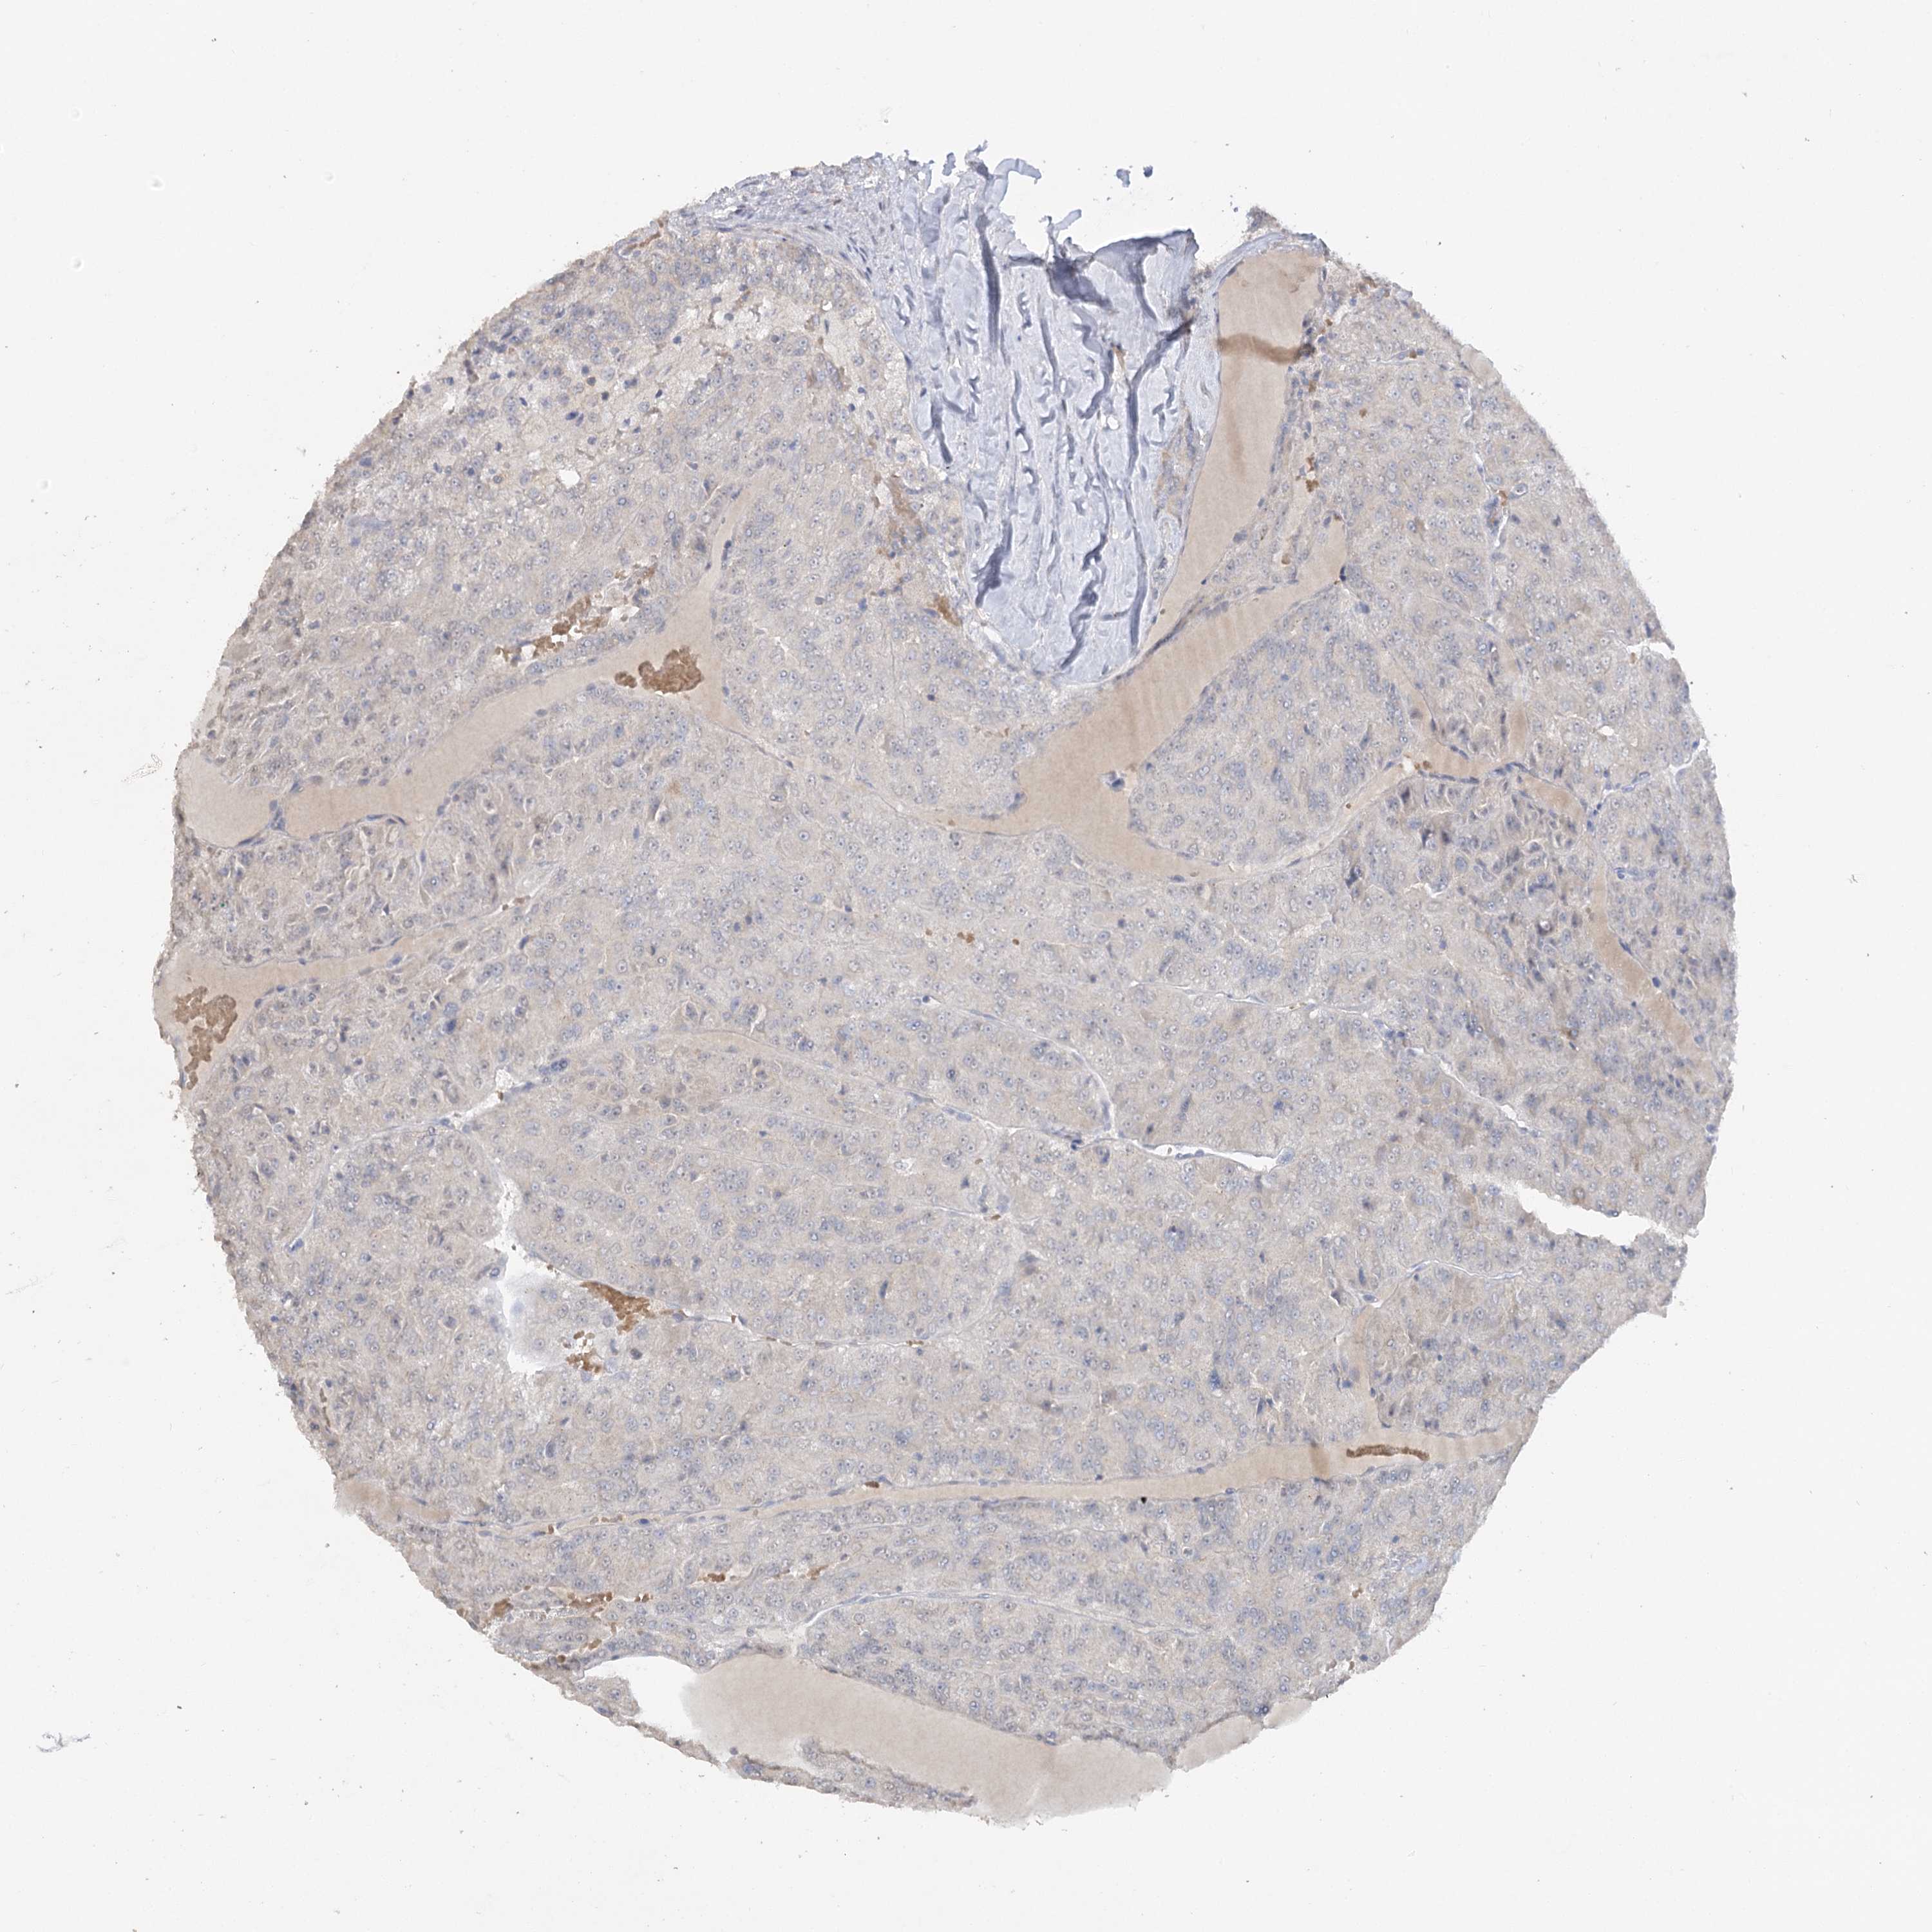

KIDNEY RENAL CLEAR CELL CARCINOMA (VALIDATION) - Interactive survival scatter ploti

TRAF3IP1 is not prognostic in Kidney Renal Clear Cell Carcinoma (validation)

: 10.79

Average pTPM 9.8

Number of samples 100